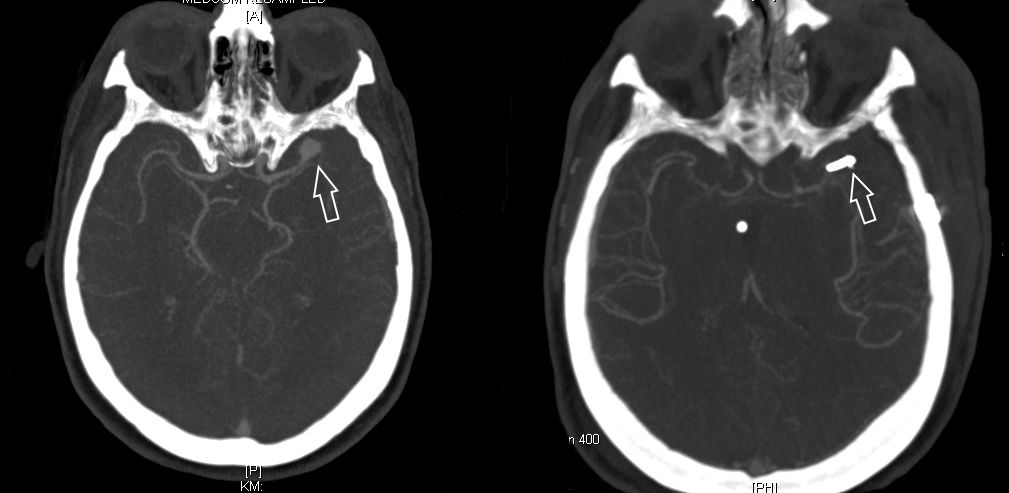

Als schnellste und sicherste Maßnahme gilt das craniale Computertomogramm (CCT). Hier lässt sich eine frische SAB meist zuverlässig darstellen, wobei auch bereits richtungsweisende Befunde, wie das Ausmaß der Blutung und eine eventuelle Lokalisation eines möglichen Aneurysmas bestimmt werden können. Darüber hinaus kann ein Angio-CCT, bei dem zusätzlich Kontrastmittel verabreicht wird und dann die intrazerebralen Blutgefäße gesondert rekonstruiert und dargestellt werden, weitere Informationen liefern. Der sogenannte “Goldstandard” zur Diagnose zerebraler Gefäßmissbildungen ist jedoch die zerebrale Angiographie. Dabei wird mit Hilfe eines speziellen Katheters über die Leisten- oder Armarterie Kontrastmittel gegeben und die zerebralen Blutgefäße hoch selektiv dargestellt. Sollten sich auf dem initialen CCT Zeichen des Hirnwasseraufstaus zeigen, der durch ein Verstopfen der Abflusskanäle durch das neu aufgetretene Blut bedingt ist, ist oft die Anlage einer Hirnwasserableitung nach außen notwendig (externe Ventrikeldrainage).

CT Bildgebung der klassischen subarachnoidalen Blutverteilung nach SAB

CT-Angiographie eines gebluteten Aneurysmas

Als diagnostische Maßnahme wird in der Regel ein craniales Computertomogramm (CCT) durchgeführt. Intrazerebrale Blutungen lassen sich mit dieser Methode sicher diagnostizieren.